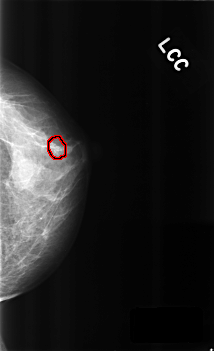

C_0300_1.LEFT_CC

LEFT_CC LINES 4560 PIXELS_PER_LINE 2776 BITS_PER_PIXEL 12 RESOLUTION 50 OVERLAY

FILE: C_0300_1.LEFT_CC.OVERLAY

TOTAL_ABNORMALITIES 1

ABNORMALITY 1

LESION_TYPE CALCIFICATION TYPE PLEOMORPHIC DISTRIBUTION CLUSTERED

ASSESSMENT 4

SUBTLETY 3

PATHOLOGY BENIGN

TOTAL_OUTLINES 1

BOUNDARY